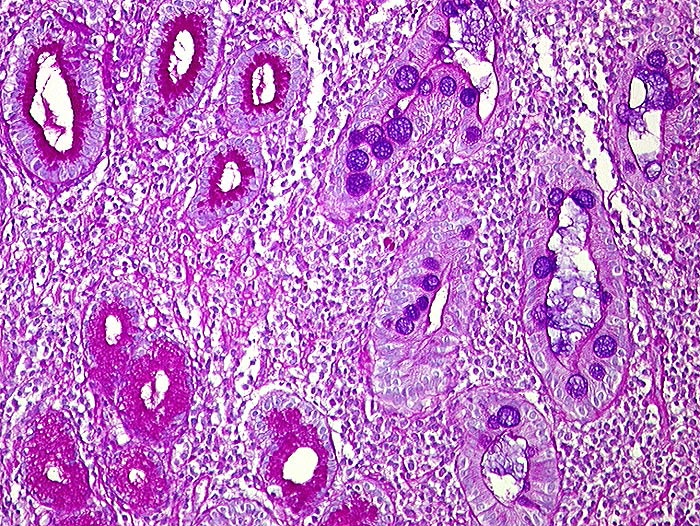

Intestinale Metaplasie

Metaplasie / Heterotopie

Magenantrum

Oesophagus, Magen

Links PAS positive Schleimdrüsen des Magenantrums. Rechts metaplastische Drüsen, welche alcianblaue Becherzellen enthalten. Dicht entzündlich infiltriertes Stroma.

Histologie